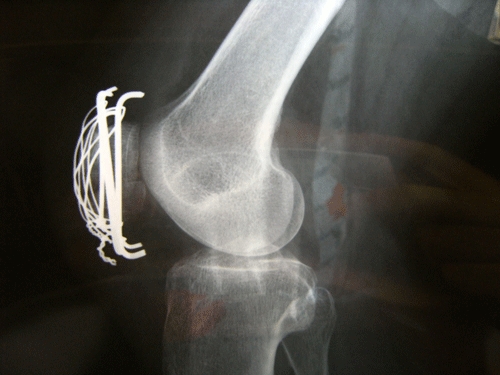

DSCF2041.gif術後25日目。

DSCF2042.gif筑波メディカルセンターへの紹介状を書いて頂く。